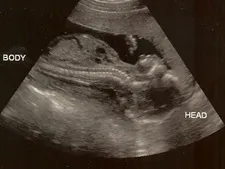

Conrad Morris (see here with his wife, the couple is expecting a baby boy soon) shares how he was able to quit smoking gradually using his PDA and some simple software.